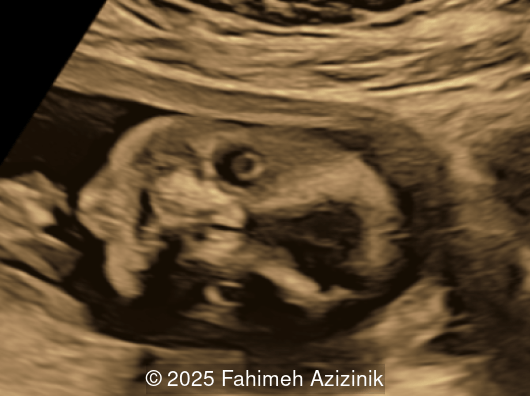

Image 2

• Hypertelorism

• Frontal bossing

Bicoronal synostosis is the characteristic cranial hallmark of Apert syndrome, detectable sonographically from 18 weeks. Its most recognizable manifestation is turribrachycephaly, defined by an elevated cephalic index (typically >85–90%) and a tall cranial vault with marked frontal bossing [19]. On prenatal ultrasound, the face in Apert syndrome shows midface hypoplasia with a depressed nasal bridge, proptosis, hypertelorism, and frontal bossing. The extremities demonstrate syndactyly of both bone and soft tissue of the hands and feet with partial-to-complete fusion often involving second, third, and fourth digits, known as “mitten hands” and “socked feet”. In severe cases, all digits are fused, with the presence of a single nail known as “synonychia” [20]. Other ultrasound findings include mild ventriculomegaly, agenesis of the corpus callosum, deficient or absent septum pellucidum, and fusion of the cervical vertebrae at the level of C5-C6 [21]. Cardiovascular (atrial and ventricular septal defect) and genitourinary anomalies (hydronephrosis, and cryptorchidia) are present in 10% of patients [22]. Increased nuchal translucency in the first trimester [23], widely open metopic suture [24], and polyhydramnios [25] have also been reported. Three-dimensional (3D) ultrasound facilitates assessment of surface abnormalities of the face and extremities, and magnetic resonance imaging (MRI) can be used to evaluate associated intracranial conditions [26].